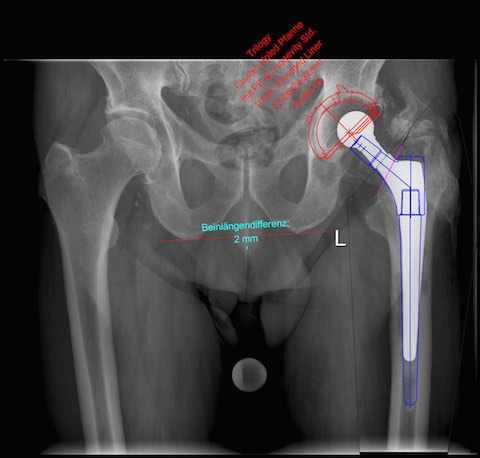

Abb. 2: Planung der Hüft-TEP-Wechsel-Operation.

Abb. 3: Ausführung der Operation: Die Lockerung an Schaft und Pfanne konnte intraoperativ bestätigt werden. Deshalb wurde sowohl die Pfanne als auch der Schaft gewechselt. Schrauben helfen die Pfanne sicher zu verankern. Außenseitige Verknöcherungen, welche die Beweglichkeit eingeschränkt haben, wurden abgetragen.